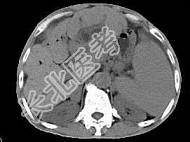

- 单项选择题根据所提供的图像,最可能的诊断是 ( )

A、肝囊肿

B、肝脓肿

C、肝胆管细胞癌伴肝硬化

D、肝细胞癌

E、以上都不是